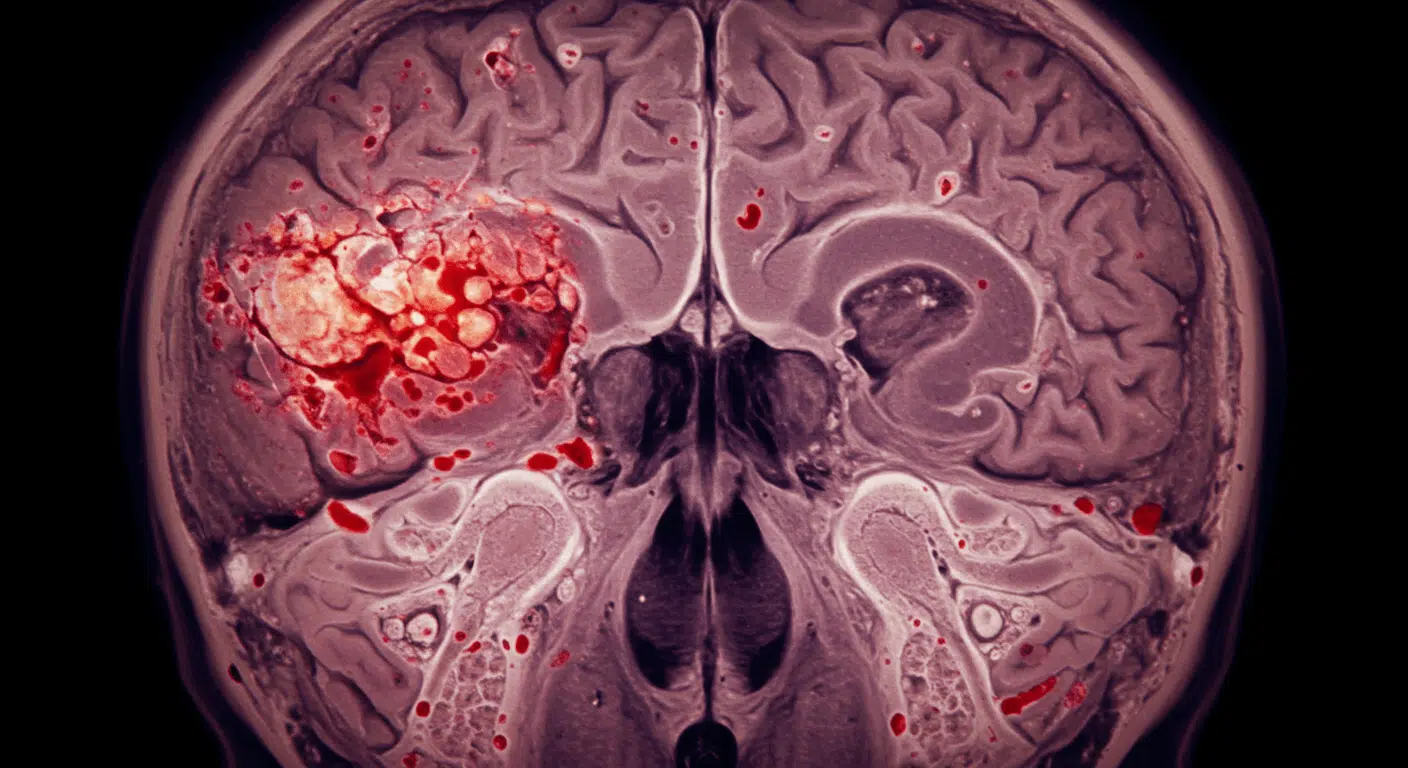

- Contusions (Brain Bruises) – A contusion is a direct impact injury that causes brain bleeding and swelling, sometimes requiring surgery to relieve dangerous pressure.

- Subarachnoid Hemorrhage – Torn arteries release blood around the brain, which can cause severe headaches, seizures, confusion, or sudden loss of consciousness.

- Subdural Hematoma – Blood pools between the brain and skull, putting pressure on brain tissue; symptoms may be delayed but can be fatal without treatment.